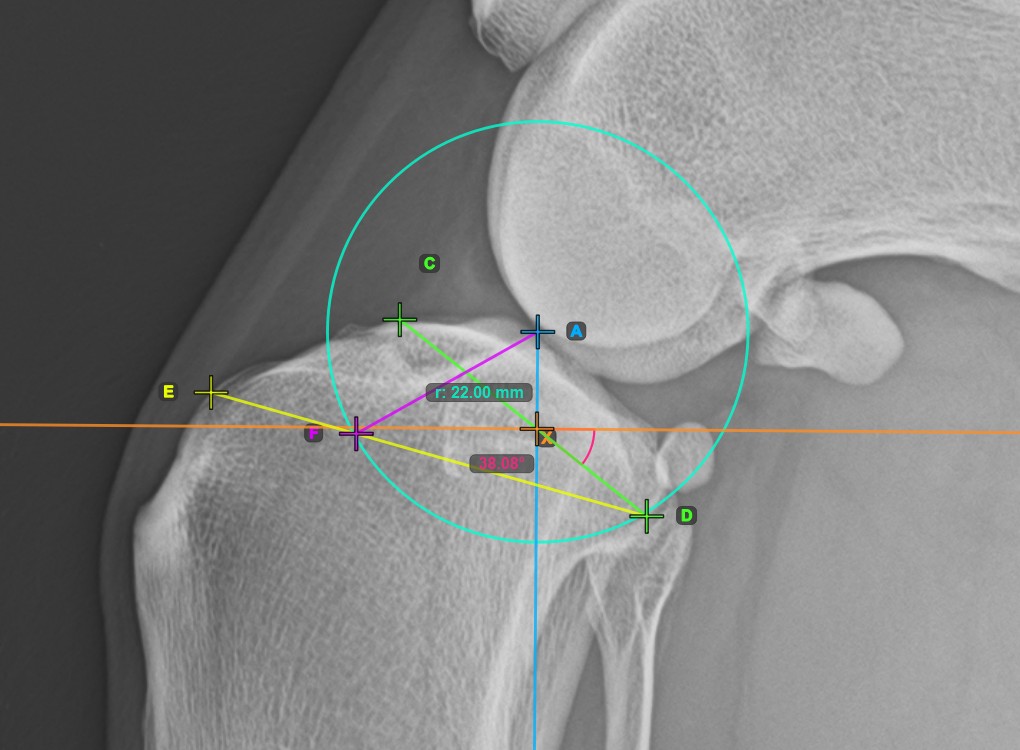

Vervollständigen Sie die TPA-Winkel-Messung, indem Sie den hintersten Punkt des Tibiakopfes (Tibiaplateau) markieren. Der TPA-Winkel wird automatisch als der Winkel zwischen der Linie, die die beiden Punkte am Tibiaplateau verbindet, und der senkrechten Linie zur Längsachse der Tibia berechnet.

Das Bild unten zeigt die übliche Platzierung des hintersten Punkts am Tibiaplateau und die automatisch berechnete TPA-Winkel-Messung.

Starten Sie die TPLO-Erweiterung, indem Sie den Tibiakamm markieren. Die Größe der Sägeblattklinge für die TPLO-Erweiterung wird automatisch als Abstand zwischen der Eminentia Intercondylaris und dem Punkt berechnet, der zwei Drittel entlang der Linie zwischen dem hintersten Punkt des Tibiakopfes und dem Tibiakamm liegt.

Drücken Sie Rotationsstrecke berechnen, um die erforderlichen Berechnungen für das TPLO-Verfahren durchzuführen. Die berechnete Rotationsstrecke wird in der Symbolleiste des erweiterten Messmodus angezeigt.